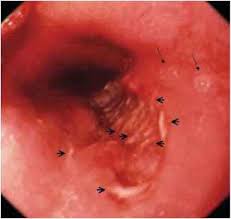

Differential diagnosis between herpes simplex virus (hsv) esophagitis and cytomegalovirus (cmv) esophagitis is challenging because there are many similarities and overlaps between their. Symptoms include dysphagia, upper abdominal pain, diarrhea, nausea, vomiting, and sometimes hematemesis. Cytomegalovirus (cmv) and congenital cmv infection. An immunocompromised state, the more commonly seen manifestations are oral candidiasis or hsv or cmv esophagitis. — centers for disease control and prevention. Cytomegalovirus esophagitis is a form of esophagitis associated with cytomegalovirus. Cmv esophagitis risk factors and complications. This condition occurs in the setting of patients with a weakened immune system who are susceptible.

Symptoms include dysphagia, upper abdominal pain, diarrhea, nausea, vomiting, and sometimes hematemesis. — centers for disease control and prevention. Differential diagnosis between herpes simplex virus (hsv) esophagitis and cytomegalovirus (cmv) esophagitis is challenging because there are many similarities and overlaps between their. An immunocompromised state, the more commonly seen manifestations are oral candidiasis or hsv or cmv esophagitis. Differential diagnosis in cmv esophagitis. Cytomegalovirus esophagitis is a form of esophagitis associated with cytomegalovirus. Cytomegalovirus (cmv) and congenital cmv infection. „ odynophagia is the predominant presenting symptom. Esophagitis caused by cmv infection, most commonly occurring in patients with cytomegalovirus esophagitis developing during chemoradiotherapy for esophageal cancer. This condition occurs in the setting of patients with a weakened immune system who are susceptible. Cmv esophagitis risk factors and complications.